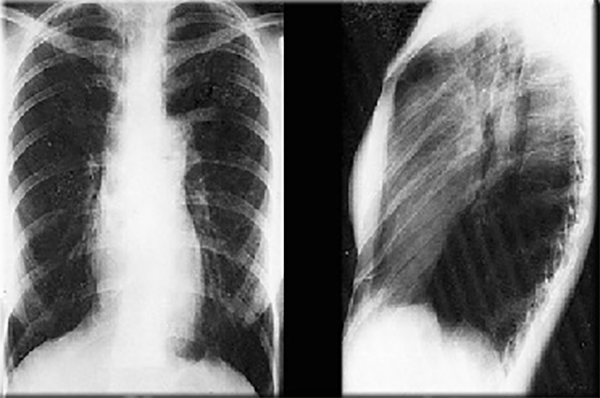

These chest X rays show a dilated pulmonary trunk and normal vascularity.

In this PA view, the dilated pulmonary trunk is demonstrated by the convex density below the aortic knob.

Note also that there is dilation of the left pulmonary artery, but that the remainder of the pulmonary arterial markings is normal. Heart size is also normal. These chest X rays are consistent with pulmonary valve stenosis.